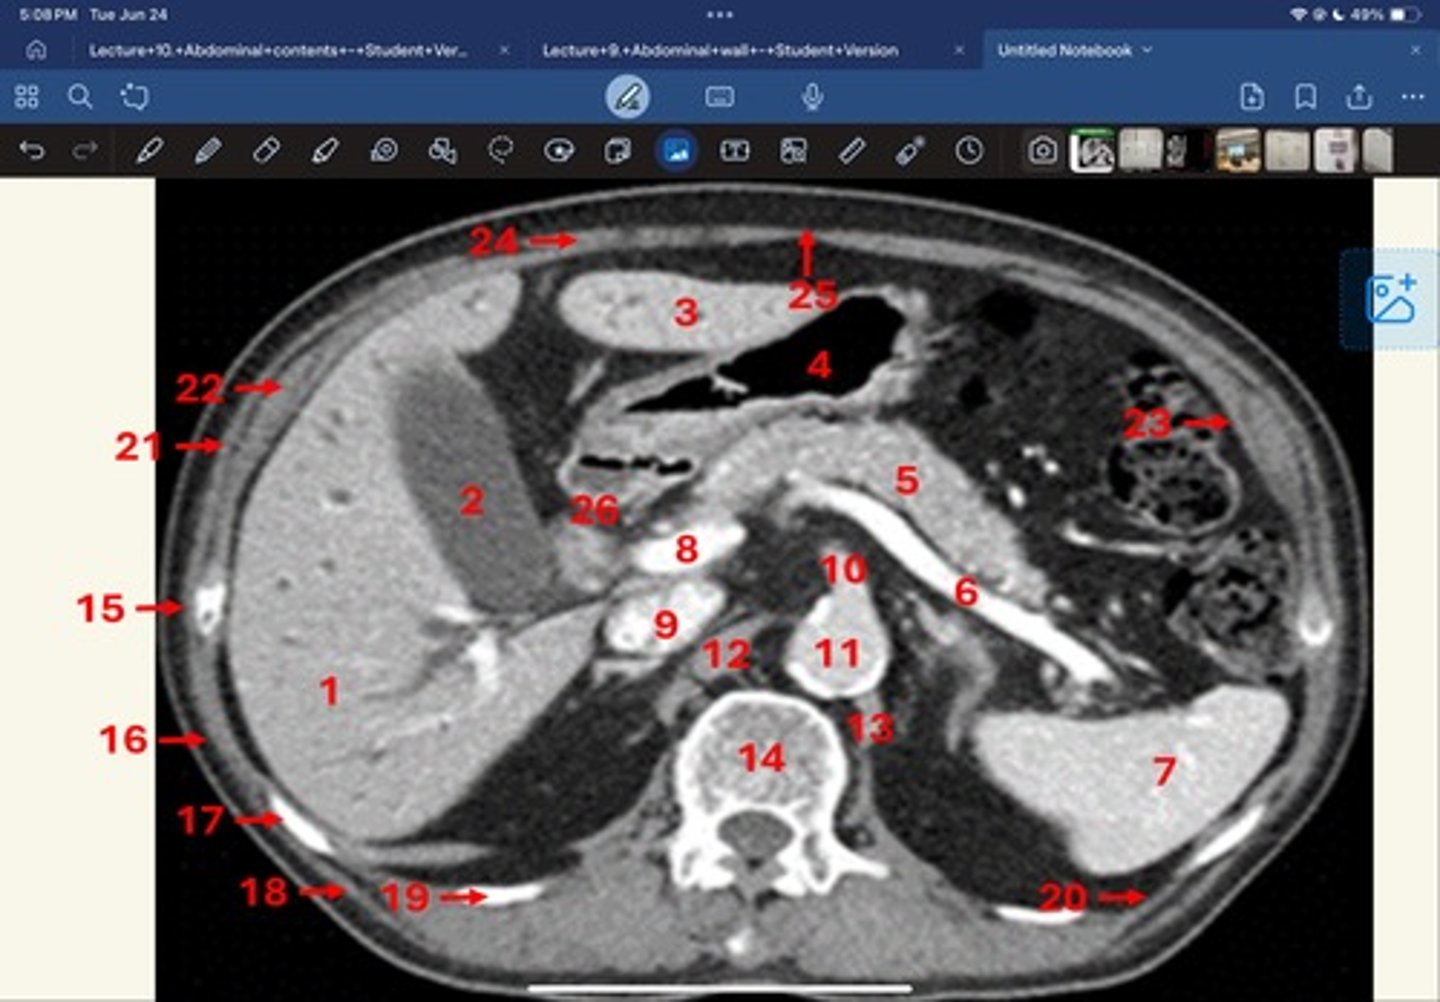

Right lobe of liver

What is 1

Gallbladder

What is 2

Left lobe of liver

What is 3

Stomach, pylorus

What is 4

Pancreas

What's 5

Splenic vein

What's 6

Spleen

What's 7

superior mesenteric vein

What's 8

Inferior vena cava

What's 9